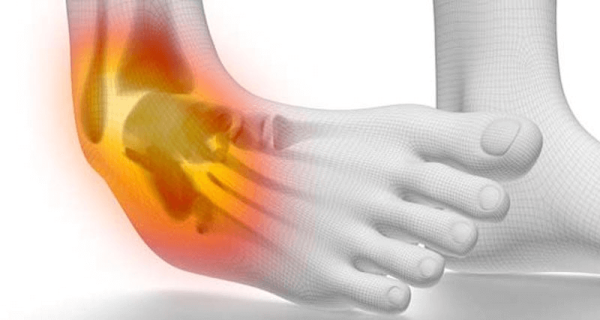

Sprain은 인대가 비정상적으로 늘어나거나 찢어진 손상을 의미합니다. 인대(Ligament)는 아주 강력한 섬유결합조직으로 관절내 2개의 뼈를 연결하고 묶어주는 역할을 합니다. 우리 주변에서 […]